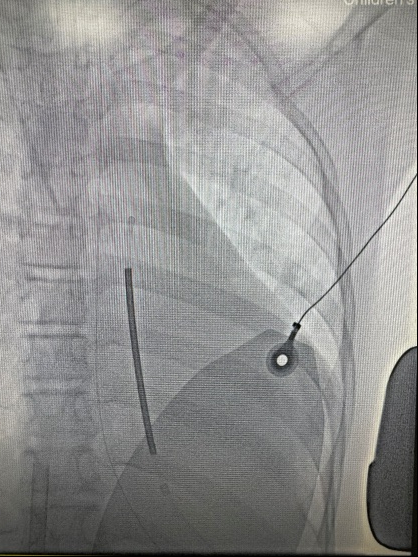

术前DSA透视体表定位(图 2),行腋中线第4~6肋间纵切口及剑突上3 cm横切口,以隧道针将除颤导线感知环头端送至胸骨柄,除颤器(波科S-ICD A209)与导线相连后置于囊袋固定。程控显示导线感知、高压阻抗正常。选择Secondary为感知向量,DFT测试:以50 Hz直流电诱发室颤,S-ICD以65 J一次转复,时长共14 s(图 3),高压阻抗37 Ω。无血管活性药物应用下暂停ECMO,心超评估EF 64%,心率100次/min,血压92/43 mmHg,SpO2 99%,撤离ECMO。术后1 d撤离呼吸机,患儿神志清,反应可,对答切题,四肢活动良好,术后6 d转入心衰病房,2024-01-23出院,住院共32 d。本文报道已取得患者监护人知情同意,伦理审批号为2020-IRB-006。

| 图 2 透视体表定位S-ICD以及导线位置 |